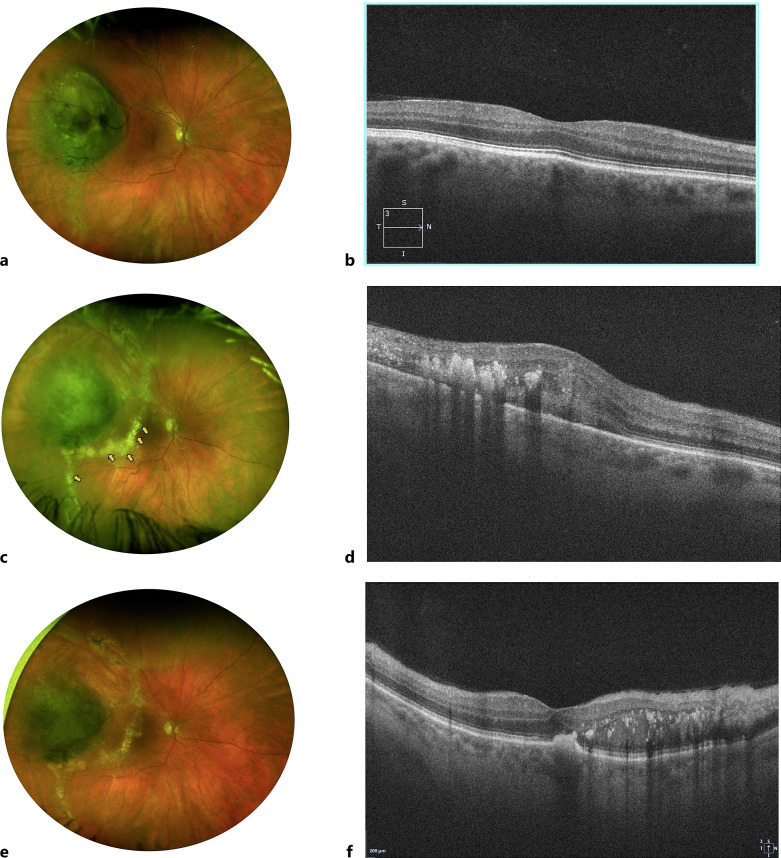

Introduction: The aim of the study was to describe clinical features of lipid dominant toxic tumor syndrome (TTS) and report outcomes following use of intravitreal steroids.

Methods: Records of 13 patients who had lipid dominant TTS following treatment of choroidal melanoma with episcleral plaque brachytherapy (EPB) were retrospectively reviewed. Resolution of lipid exudates, subfoveal subretinal fluid, cystoid macular edema (CME), exudative detachment were main outcome measures.

Results: Of the 13 patients who developed lipid dominant TTS, 11 (85%) had medium-sized melanomas, and 2 (15%) small-sized melanomas. The average time to onset following EPB was 22 months (range 3-48 months). Seven patients (54%) were noted to have dyslipidemia. The baseline visual acuity at the time of diagnosis of TTS was 50 ETDRS letters (range 10-85). Ophthalmic characteristics were lipid exudates centered around the tumor base in 13 (100%) patients, subfoveal subretinal fluid in 4 (31%) patients, and CME in 2 (15%) patients. Exudative detachment was absent in all (100%) patients. Regressed melanoma was present in all (100%) patients. Eight (62%) patients were treated with intravitreal steroids (4 mg triamcinolone), while 5 patients (38%) were observed. The response to intravitreal steroids was noted in 7(88%) of the treated patients, with the average time to response being 1.9 months. Features characterizing a positive response were reduction in lipid exudates centered around the tumor base (100%), reduction in subfoveal subretinal fluid (100%), and reduction in CME (50%). Cataract development was seen in 10 (83%) and ocular hypertension in 3 patients (23%). Proliferative radiation retinopathy developed in 2 (15%) patients, neovascular glaucoma developed in 1(8%) while no patients required enucleation.

Conclusion: The lipid dominant TTS centered around the tumor base that occurs in a radiation responsive tumor could be considered a chronic variant in the spectrum of TTS. Intravitreal steroids in selected cases reverse the course of this variant, stabilizing or improving the vision and avoiding enucleation. Our observations would need to be verified through a larger prospective study.